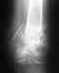

Да нисколько не надо, от аппаратной физиотерапии здесь не приходится ожидать никакого проку. Насчет нагрузок - после прекращения гипсовой иммобилизации сделают снимки, и далее будут делать с интервалом 2-3 недели. По мере увеличения прочности костной спайки можно будет увеличивать нагрузки. Месяцам к 2-3 должно срастись.